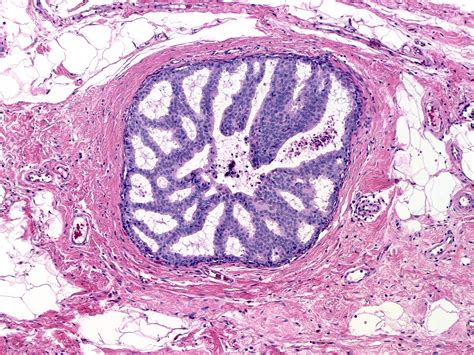

To understand Atypical Ductal Hyperplasia, it helps to look at how breast tissue changes. In a healthy breast, cells line the ducts (the tubes that carry milk). Sometimes, these cells begin to grow in an uncontrolled or disorganized manner. This process is called hyperplasia.

When those cells not only multiply but also begin to look and behave differently than normal cells—yet are not considered cancer—it is classified as “atypical.” Therefore, ADH represents a state of overgrowth where the cells lining the breast ducts have acquired some features of cancer but remain confined within the ductal structure. It is essentially a marker that indicates your breast cells are prone to genetic changes that could lead to breast cancer in the future.

If a needle biopsy reveals Atypical Ductal Hyperplasia, your doctor will likely recommend an excisional biopsy (often called a surgical biopsy). This is a standard procedure because a needle biopsy only takes a tiny sample of the tissue. Sometimes, the initial biopsy may have missed a larger area of cancer or higher-grade atypical cells located elsewhere within the same lesion.

During an excisional biopsy, the surgeon removes the entire area of concern along with a margin of healthy tissue. This allows the pathologist to examine the entire lesion to confirm the diagnosis and ensure no invasive cancer is hidden nearby.